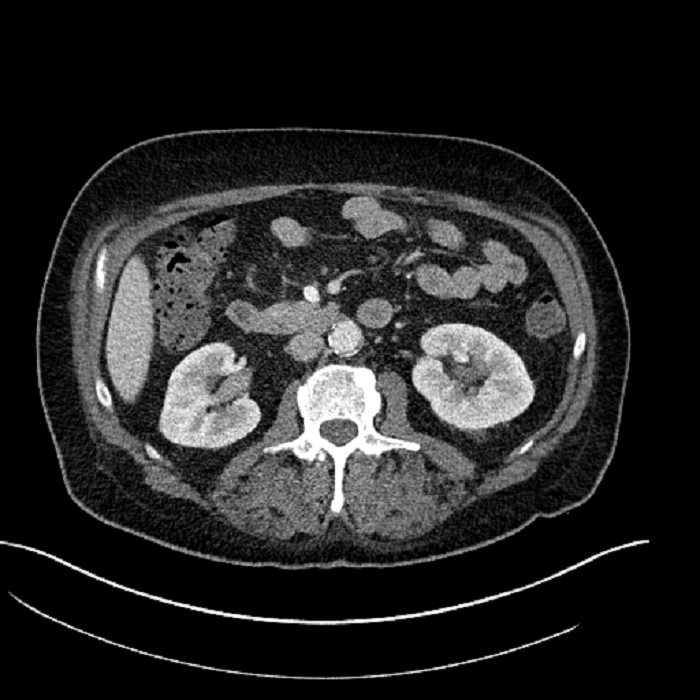

• Large fluid density structure in hepatic segments 7 and 8 measuring 10 x 7 x 7 cm with internal septation and circumferential ill-defined low density compatible with edema

• Peripherally enhancing subcapsular collections along the anterior margin of the left hepatic lobe measuring 3 x 1 cm and 2 x 1 cm

• Clearly marginated fluid density structure in segment 7 and several other scattered tiny hypodensities, which likely represent cysts

Acute sigmoid diverticulitis complicated by a small contained perforation and a large abscess in the right hepatic lobe. Additional small subcapsular abscesses along the anterior margin of the left hepatic lobe.

• The classic CT imaging appearance is a double target sign with internal low density surrounded by an internal enhancing rim (capsule) and a low density external rim (edema)

Hepatic abscess showing the double target sign with low density internally surrounded by a thin inner enhancing rim (red arrow) and ill-defined outer low density rim (yellow arrow). Blue arrow indicates an internal septation. Red arrows: additional smaller subcapsular abscesses. Red arrow: focal contained perforation associated with diverticulitis.